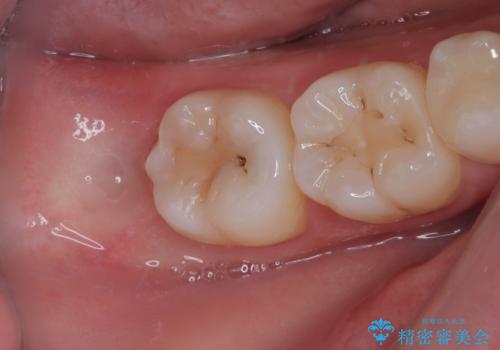

親知らずを抜きたい 親知らず抜歯

右下の親知らずを抜きたい 親知らず抜歯